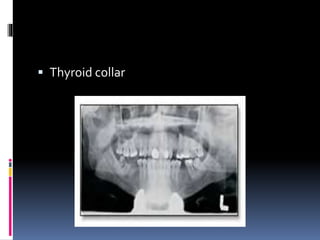

 Thyroid collar